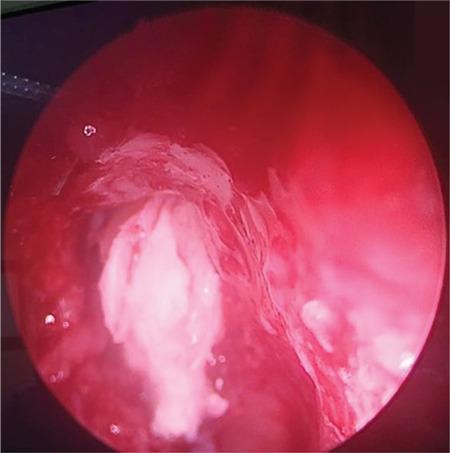

Frontal sinus keratoma or cholesteatoma is a rare disease of paranasal sinuses and presents as a slow-growing mass that becomes symptomatic as it grows to the surrounding structures. Intracranial complications are not a common presentation and are potentially life-threatening. Frequently the final diagnosis is only made intraoperatively because several other frontal sinus tumors behave likewise. Definitive treatment requires complete removal of the keratoma, and a combined endoscopic and external frontal sinus approach is a good treatment option. In this report, we presented a 68-year-old female with frontal sinus cholesteatoma with diagnostic and therapeutic features of this pathology with the review of the literature.